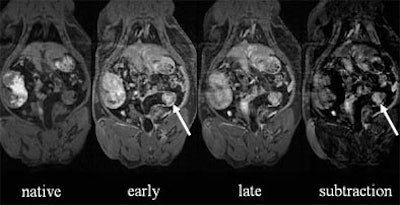

| Native dataset (left) again offers little detail, but strong contrast uptake in arterial-phase enhancement reveals a large lesion in the sigmoid colon. Data subtraction technique further increases lesion conspicuity. |